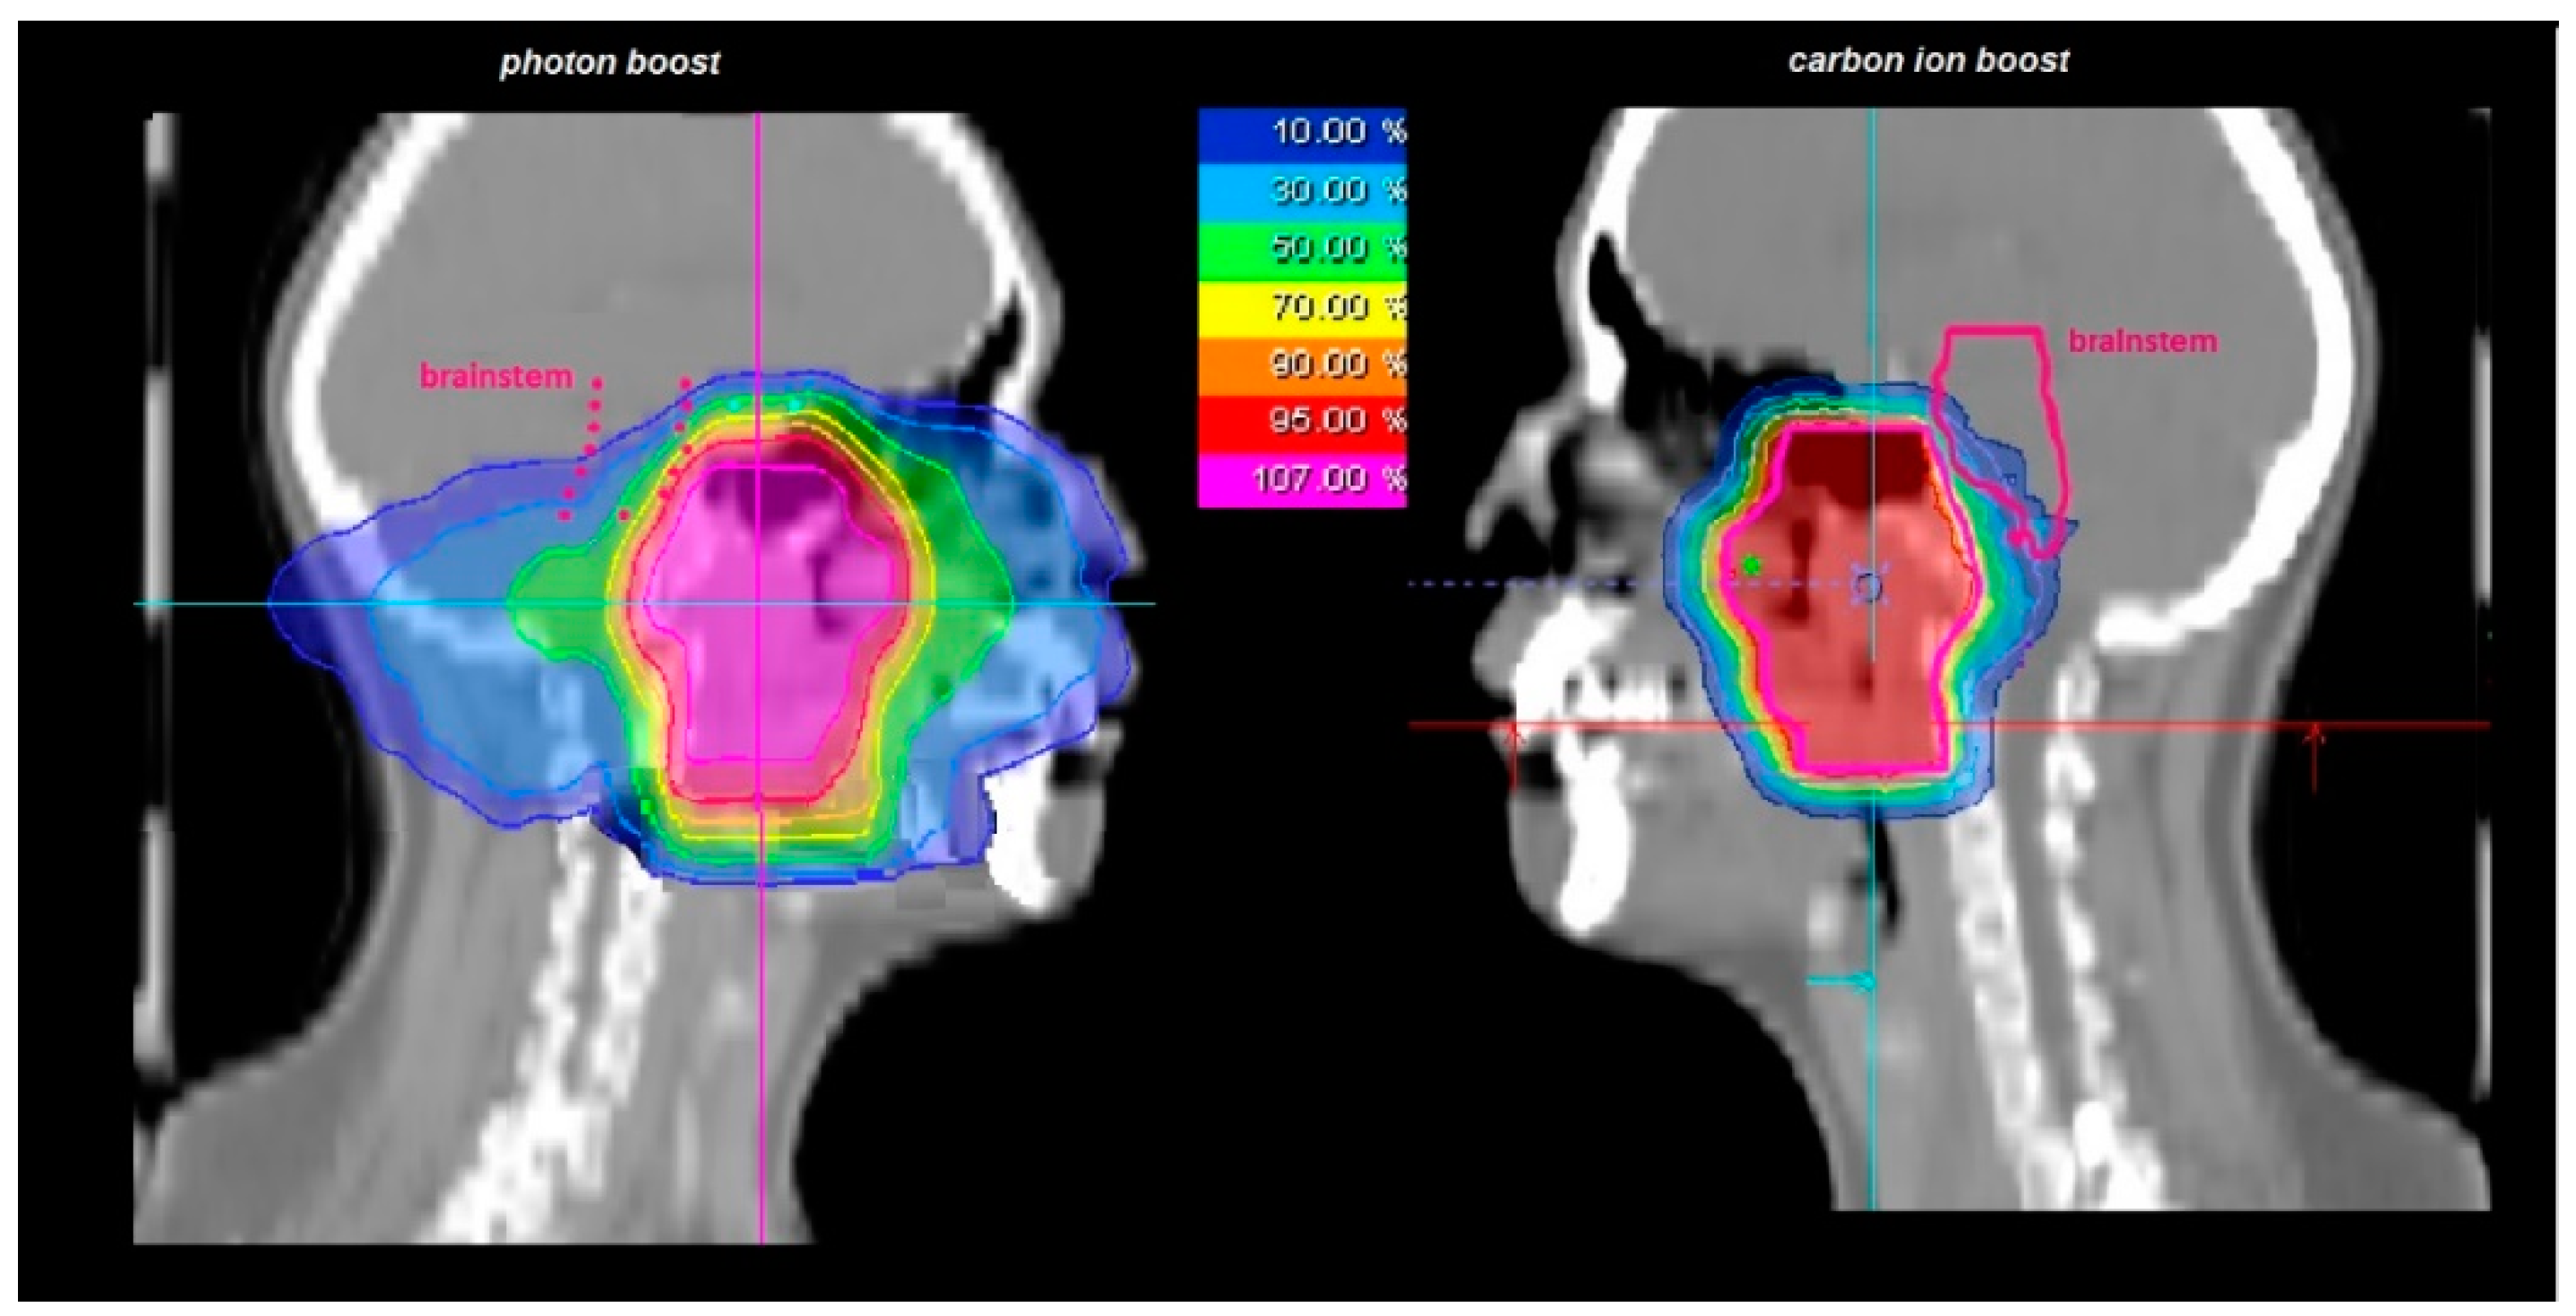

| 50 Gy/2 Gy IMRT + 24 Gy/3 Gy (RBE) C12 | 5 (19) |

| 56 Gy/2 Gy IMRT + 18 Gy/3 Gy (RBE) C12 | 21 (81) |

| median total dose | 74 Gy (RBE) (72–74 Gy (RBE)) |